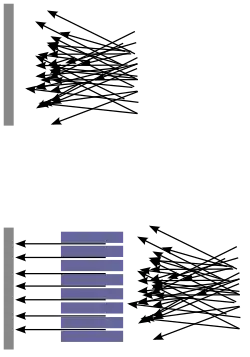

Bei der Einzelphotonen-Emissions-Tomografie (SPECT) wird ein Kollimator benötigt, um die Strahlrichtung der zu messenden Photonen bestimmen zu können. Da dieser einen Großteil der Photonen ausblendet, wird nur etwa je 1 von 10.000 emittierten Photonen nachgewiesen. Bei der PET kann dagegen durch das Messprinzip des Koinzidenznachweises auf eine physikalische Kollimation verzichtet werden, was zu einer um ca. hundertmal höheren Zählausbeute und somit verbesserter Bildstatistik mit höherer Bildqualität und räumlicher Auflösung führt.[1] Die Absorption der gemessenen Photonen hängt nur von der Dicke des durchstrahlten Gewebes ab, nicht jedoch vom Entstehungsort der Photonen (siehe Korrektur der Messdaten, Abschnitt Absorptionskorrektur). Dies ermöglicht eine genaue Quantifizierung der Tracerverteilung im Untersuchungsvolumen, was mit der SPECT nicht möglich ist.[2]

Der 2D-Aufnahmemodus

Neben dem 3D-Modus verfügten einige Geräte bis etwa bis zum Ende der 2000er Jahre noch über einen 2D-Aufnahmemodus. Hierbei werden nur die Ereignisse auf Koinzidenz geprüft, die sich in Kristallen desselben Detektorringes ereignen. Man unterscheidet weiter zwischen einem „elektronischen“ und einem „echten“ 2D-Modus: Beim „echten“ 2D-Aufnahmemodus werden Wolframsepten in die Gantry eingefahren, um Photonen, die nicht streng radialen Ursprungs sind, zu stoppen. Beim „elektronischen“ 2D-Modus wird durch Verschaltung der Koinzidenzprüfung nur auf Koinzidenzen innerhalb desselben Ringes geprüft, die Strahlung selbst bleibt aber für die Detektoren „sichtbar“. Der elektronische und der „echte“ 2D-Modus führen zu erstklassiger Homogenität der Sensitivität über das Field of View.

Das physikalische Ausblenden von schräg eintreffenden Photonen beim „echten“ 2D-Aufnahmemodus mittels Wolframsepten und Endshields verringert die Zahl der von den Detektoren „gesehenen“ Ereignisse stark; dieser Aufnahmemodus ist daher sehr effektiv für die Unterdrückung von Streustrahlung einsetzbar. Da die Detektoren nur Koinzidenzen aus radialer Richtung „sehen“, ist zudem die Wahrscheinlichkeit, dass gemessene Ereignisse Zufallskoinzidenzen sind, geringer als im 3D-Aufnahmemodus. Durch das Ausblenden schräg einfallender Ereignisse werden naturgemäß nicht nur unerwünschte Streuereignisse, sondern auch echte Koinzidenzen von den Detektoren ferngehalten. Die Sensitivität des Scanners im 2D-Modus beträgt nur etwa 20 % von der des 3D-Modus, jedoch sinkt auch der Streustrahlenanteil von über. 40 % auf ca. 10 % ab.